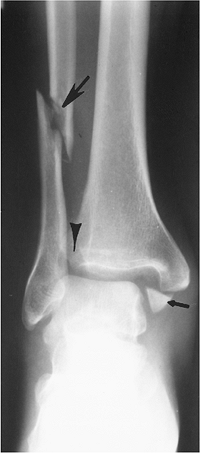

Fractures/Dislocations: Ankle Adult—Pronation Lateral Rotation Injuries

-

The medical malleolus (low transverse

fracture) or medial ligaments are injured initially (Stage I). As force

continues, the anterior tibiofibular and interosseous membranes are

torn (Stage II), followed by a high fibular fracture (more than 5 to 6

cm above the joint) (Stage III). Posterior tibial avulsion or distal

tibiofibular ligament tears occur with continued force (Stage IV) (Fig. 6-17). -

Pronation injuries account for 22% to 25% of ankle fractures.

Treatment of these fractures usually

requires internal fixation of the fibular fracture and screw fixation

of the medial malleolus.

![]() |

|

FIGURE 6-18 Pronation lateral rotation Stage IV injury with a transverse medial malleolar fracture (small arrow), disruption of the tibiofibular and interosseous ligaments (arrowhead), and a high fibular fracture (large arrow).